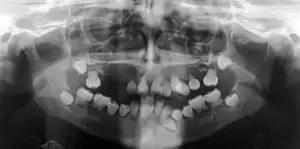

| Preoperative panoramic radiographs showing features of dentin dysplasia type I | |

Dentin dysplasia (DD) is a rare genetic developmental disorder affecting dentine production of the teeth, commonly exhibiting an autosomal dominant inheritance that causes malformation of the root. It affects both primary and permanent dentitions in approximately 1 in every 100,000 patients.[1] It is characterized by presence of normal enamel but atypical dentin with abnormal pulpal morphology. Witkop[1] in 1972 classified DD into two types which are Type I (DD-1) is the radicular type, and type II (DD-2) is the coronal type. DD-1 has been further divided into 4 different subtypes (DD-1a,1b,1c,1d) based on the radiographic features.[2]

In other words, affected primary teeth usually have abnormal shaped or shorter than normal roots. “Crescent/half-moon shaped” pulp chamber remnant in permanent teeth can be seen on x-rays. The roots may appear to be darker or radiolucent/pointy and short with apical constriction. Dentine is laid down abnormally and causes excessive growth within the pulp chamber. This will reduce the pulp space and eventually cause incomplete and total pulp chamber obliteration in permanent teeth.[12][13] Sometimes periapical pathology or cysts can be seen around the root apex.[11] Most cases of DD associated with peri-apical radiolucency/ pathology have been diagnosed as radicular cysts, but some of them have been as diagnosed peri-apical grauloma instead.[14]